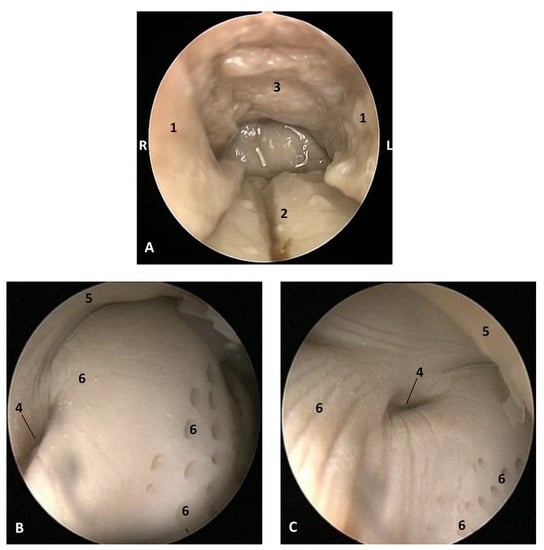

3.2. The Pharyngeal Cavity

The pharynx is a musculo-membranous cavity divided into three parts: the oropharynx linking the oral cavity with the oesophagus, the nasopharynx connecting the nasal cavity with the larynx, and the laryngopharynx, which is an intermediate cavity caudal to the oropharynx and caudoventral to the nasopharynx. The laryngopharynx connects the oral cavity to the stomach and allows the aditus laryngis enter to the nasopharyngeal cavity crossing, only in cetaceans (Figure 15), the intrapharyngeal orifice.

3.2.1. Study of Oropharynx, Nasopharynx and Laryngopharynx

The oropharynx begins at the isthmus of the fauces, continues with a conduit (fauces) and finishes at the lingual aspect of the epiglottic cartilage (Figure 15).

Figure 15. Head of a dolphin fetus, showing the pharyngeal cavity. (A) Oropharynx; (B) Laryngopharynx; (C) Nasopharynx. MRI sagittal T1 SE sequence. 10 months, dde14. 1, Isthmus of the fauces; 2, Fauces; 3, Epiglottic vallecula; 4, Piriform recess; 5, Oesophageal vestibule; 6, Intrapharyngeal orifice: 7, Oesophagus mucosa.